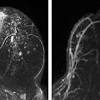

If these tests don't answer the quest. But not every woman who has been diagnosed with breast cancer needs a breast mri. Determining the extent of cancer after a new breast cancer diagnosis. It can also help detect breast cancer in women with breast implants and in younger women who tend to have dense breast tissue. An mri can be used to look for a disease, such as breast cancer. But there are also other reasons to have a breast mri. Inflammatory breast cancer affects breast tissue and can appear unusually dimpled or thick. Breast mri images are combined, using a computer, to create detailed pictures. A waiver of informed consent Mri scan is also used in breast screening for young women who are at higher risk of developing cancer. Dcis on mri may create an area of irregular enhancement of the mri dye into the breast. They're often easy to move around (mobile) and may be tender. A breast mri is a highly effective test.

They might be at higher risk due to having family members with cancer or because they have certain gene abnormalities (mutations). By comparison, only 11 out of 48 patients, or 23 percent, with all fatty hilum in place had cancer. Because the dye can affect the kidneys, your doctor may. Unlike traditional forms of breast cancer, inflammatory breast cancers do not develop unusual lumps within the affected breast. Magnetic resonance imaging (mri) of the breast — or breast mri — is a test used to detect breast cancer and other abnormalities in the breast. Mri of breast can help breast cancer diagnosis. When women undergo mris to check for breast cancer, the scans sometimes reveal suspicious masses elsewhere in the body, which can generate a lot of anxiety and require more testing. This means that the test finds a mass or other change that seems to show cancer but it is not cancer. A breast mri is a highly effective test. Palpation of benign breast masses. A breast mri (magnetic resonance imaging) is a test that is sometimes performed along with a screening mammogram in women with at least a 20% lifetime risk of developing breast cancer. You may notice dimpling or pitting, and the skin on your breast. Some benign conditions such as fibrocystic disease can look like cancer.

The Radiology Assistant Mri Of The Breast from radiologyassistant.nl Your doctor may recommend a breast mri for the following: A breast mri captures multiple images of your breast. This is why we ask questions about menstrual cycle and hormone therapies prior to your study. What does breast cancer look like on a mammogram? Dcis on mri may create an area of irregular enhancement of the mri dye into the breast. The features of a malignant breast condition on mri scan are often to do with the outer irregular borders of a lesion. An mri can be used to look for a disease, such as breast cancer. If you are at risk of getting a certain disease, your caregiver may want to do an mri to look for signs of the disease.

An mri can help find a disease of the lungs or show tumors (growths) in the chest. But not every woman who has been diagnosed with breast cancer needs a breast mri. The features of a malignant breast condition on mri scan are often to do with the outer irregular borders of a lesion. A rash isn't the only visual symptom of inflammatory breast cancer. Any area that does not look like normal tissue is a possible cause for concern. A breast mri scan might also be used to assess the size of the cancer to check which kind of surgery is possible. They work to destroy the tumor or slow down the growth of cancer cells. This appears most commonly as streaking, known as linear enhancement. On the flip side, there are benign (not cancerous) breast changes which can mimic breast cancer as well. This means that the test finds a mass or other change that seems to show cancer but it is not cancer. Breast mri images are combined, using a computer, to create detailed pictures. What does breast cancer look like on a mammogram? The dye collection in the breast can also look clumpy or appear in a section of the breast, depending on the involvement of dcis.